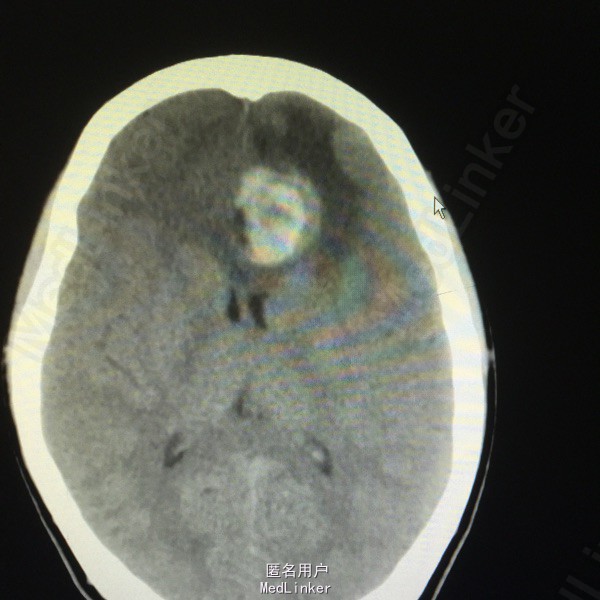

患者男,71岁。2周前无明显诱因出现双小腿困乏、记忆力下降、言语欠流利.未行特殊诊治。入院前3天出现夜间睡眠障碍,当地医院行头颅CT检查示:右额部类圆形占位性病变,密度略欠均匀,直径约5 cm。周围脑水肿.右侧侧脑室受压,中线结构略向左移。继而转来我院。

入院查体患者无发热,精神食欲较好,大小便正常,入院后系统查体其他部位未见明确异常。头颅MRI检查示:右侧额叶见一类圆形囊实性占位病灶,T1WI序列病灶囊性部分信号与脑白质信号相似,T2WI序列呈高信号,实性结节位于囊前外侧靠近脑表面呈短T1等T2信号,病灶境界尚清,外周环绕片状稍长T1长T2水肿信号,局部脑沟变浅消失。右侧侧脑室前角受压;增强示:右侧额叶病灶呈环形不规则强化,局部结节较大明显强化,病灶大小约为4.0 cm×4.2 cm×5.0 cm。

右侧额叶占位合并出血,考虑:胶质瘤中多形性胶质母细胞瘤或间变型星形细胞瘤,不除外脑转移瘤。